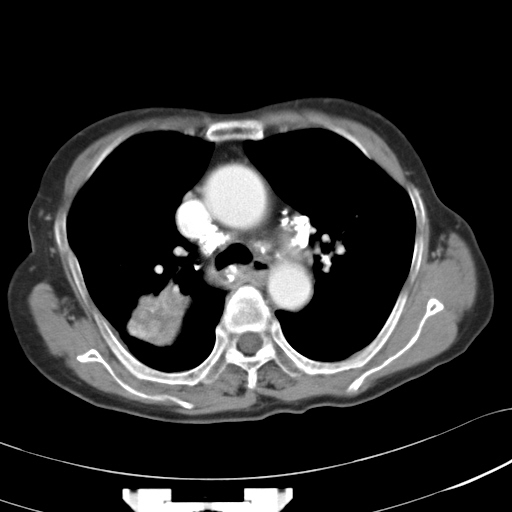

以下是引用hhcckk在2007-3-2 14:51:00的发言:[br]考虑结核球可能性大,依据[br]1病灶在下叶背段,结核的好发部位[br]2病灶内有大量的钙化,纵隔内有大量的淋巴结钙化[br]3重要的是半年前与现在相比无变化,假如是肿瘤的话不会这么‘善良’[br]4病灶周围卫星灶不明显,病灶有毛刺,胸膜凹陷,肿瘤不能完全排除,有条件的话最好做个活检

以下是引用liuyue在2007-3-2 17:15:00的发言:[br]1位置:右上叶后段[br]2性质:大分叶、粗长毛刺、条状斑片状钙化、纵隔多发淋巴结钙化,无强化,故考虑:肺结核灶(陈旧)